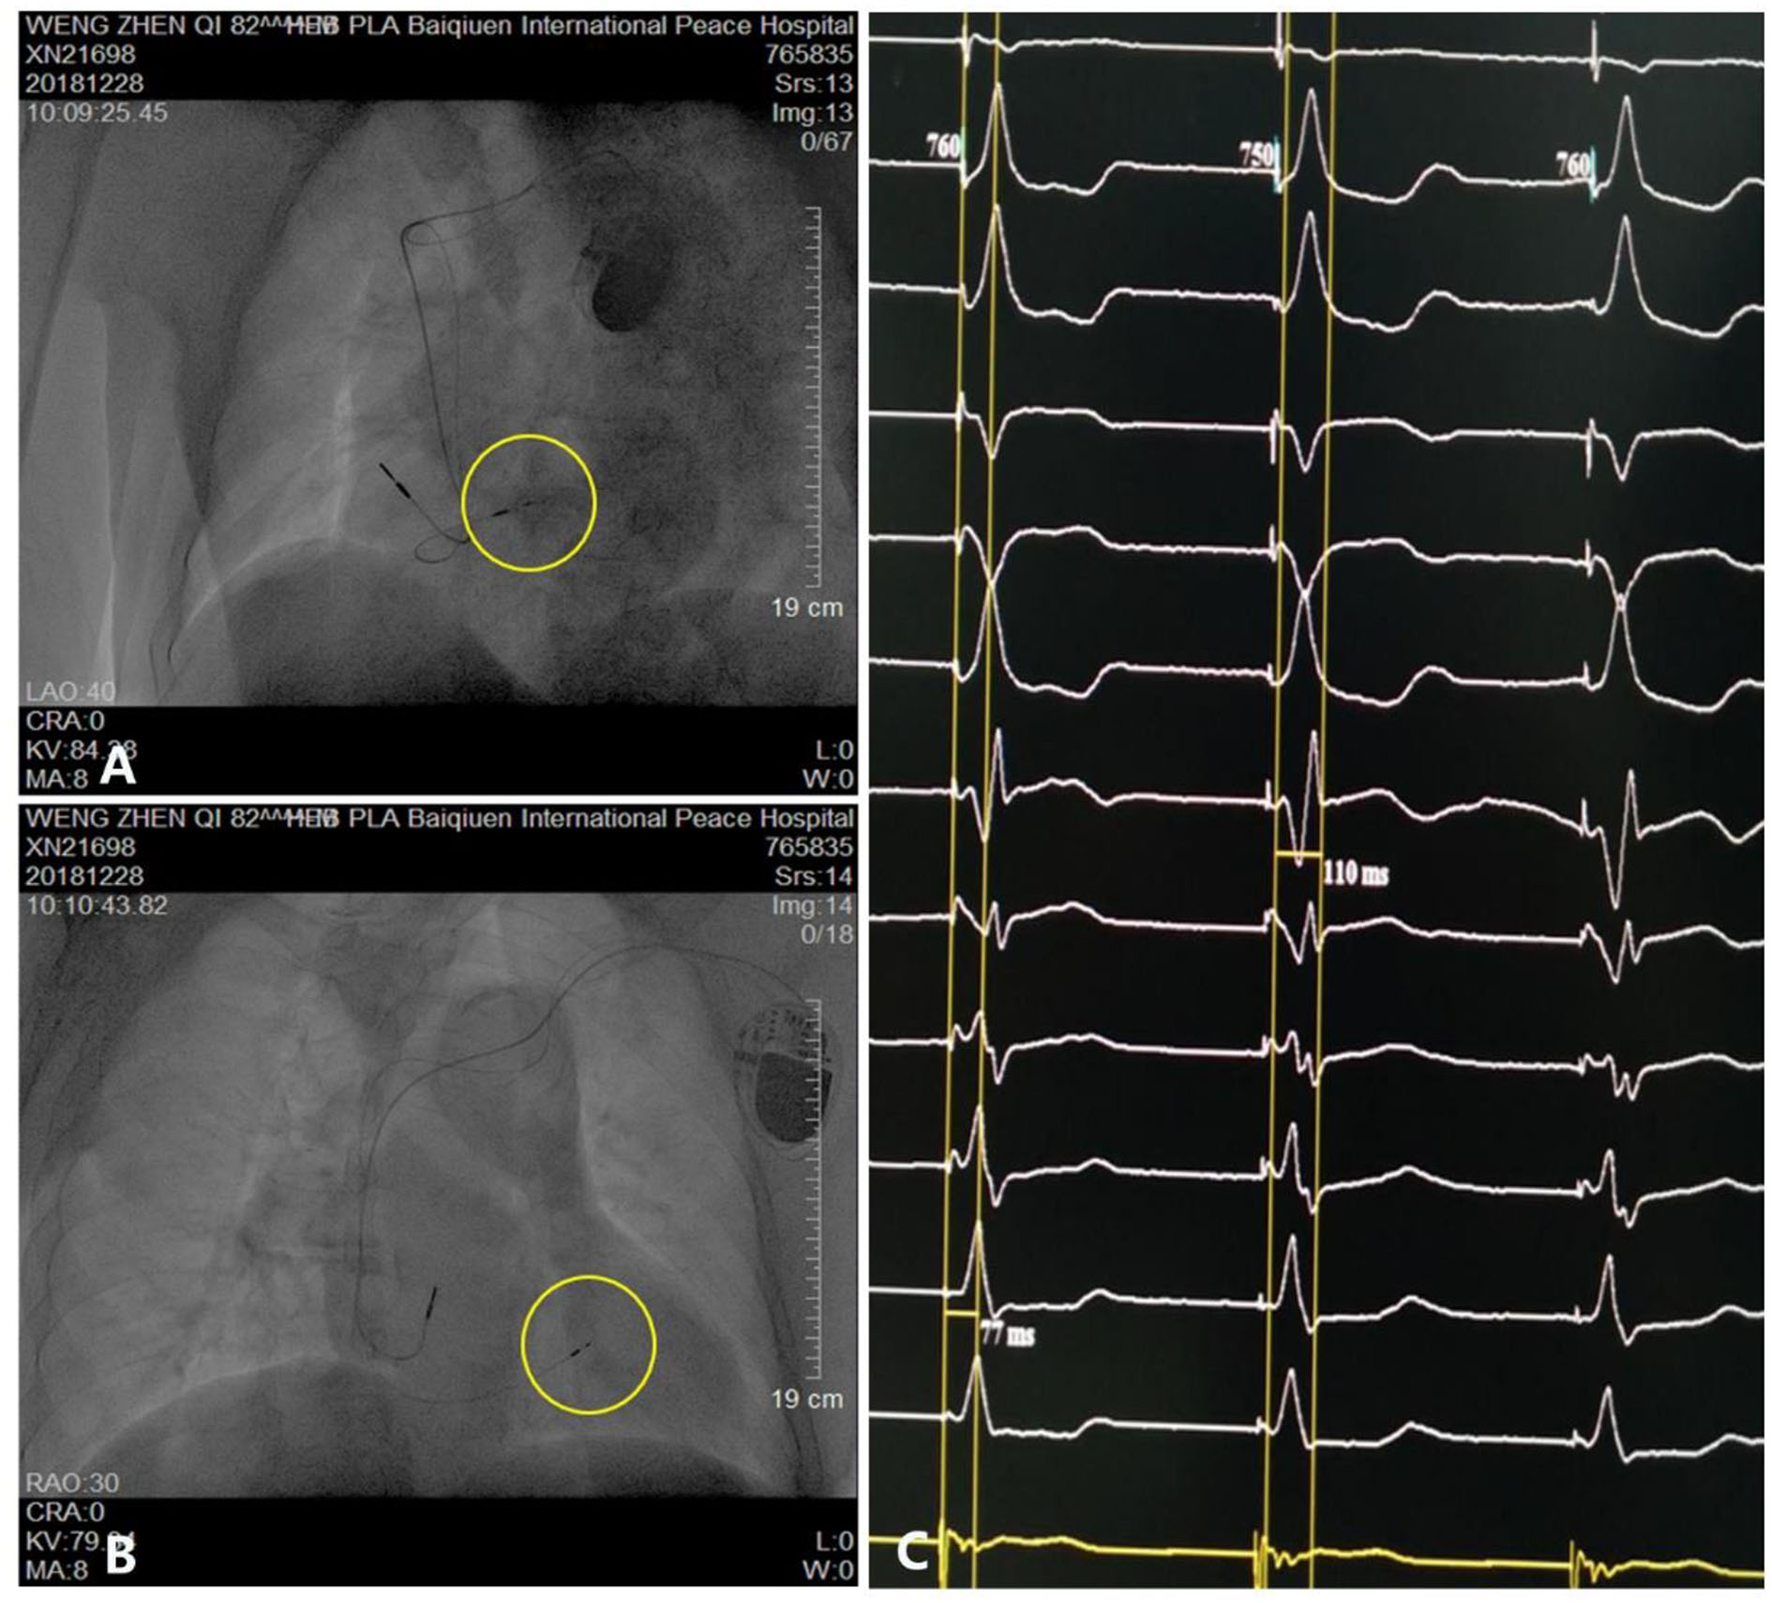

Figure 3

Parameters and visualization of pacemaker implantation. (A,B) Pacing electrode of the left bundle branch (yellow circle). (C) Electrocardiogram showing a QRS duration of 110 ms.

The patient underwent LBB pacemaker implantation for second-degree type II AV block according to the treatment guidelines. A 3,830 lead (Medtronic, Inc. Minneapolis, MN, US) was advanced and positioned via a transventricular septal approach (Figures 3A,B). The procedure was performed successfully, with a pacing threshold of 0.5 V/0.4 ms and a QRS duration of 110 ms on the ECG (Figures 1A,C, 3C). The pacemaker had a normal function in subsequent examinations until the occurrence of AMI (Table 1). Compared with the previous ECG, there was a transient loss of capture and an increase in the LBBP threshold at the time of AMI (Figure 1B; Table 1). Pectoral muscle twitching was noted which indicated some changes in the electrical performance of the pacing system. The pacemaker and electrode were immediately tested; the ventricular pacing threshold had increased to 5 V/0.4 ms (Table 1) whereas that of the right atrium remained stable compared with the value recorded at implantation. After parameters adjustment, the symptoms disappeared and the threshold decreased to 3.5 V/0.4 ms. Three days after AMI, in the absence of additional acute ischemia, the pacing threshold had decreased to 2.5 V/0.4 ms and was stable. The LAD PCI was performed after 2 weeks (Table 1). A 3.5 × 28 mm drug-coated stent (Boston Scientific, Marlborough, Massachusetts, US) was placed in the proximal segment of the LAD (Figures 2D–F). A routine test showed that the pacing threshold had decreased to 2 V/0.4 ms (Figure 1D, Table 1).